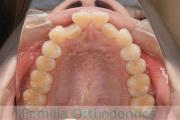

No.19V-044

- 主な症状:

- 上顎前突

- 年齢:

- 13歳

- 性別:

- 女性

- 抜歯部位

- 上:

- 44

- 下:

- 8558

- 主な使用装置:

- FEA

- 治療にかかった費用:

- 85万円

出っ歯を治したいということで小学生の時に来院されました。中学生になるまで経過観察をして、診断、上下左右から小臼歯を抜歯してマルチブラケット法にて治療を行いました。2年強、30回程度の通院が必要でした。

口元の突出感も大きく改善しています。

- ≫治療前

- ≫治療後

上下とも前歯の叢生(でこぼこ、凹凸、ガタガタ)がありましたので、保定をしっかりやらないと後戻りのリスクが出てきます。